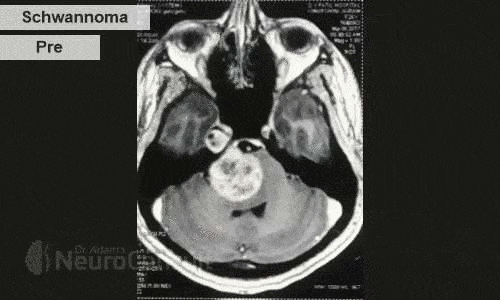

My Cases Studies & Work